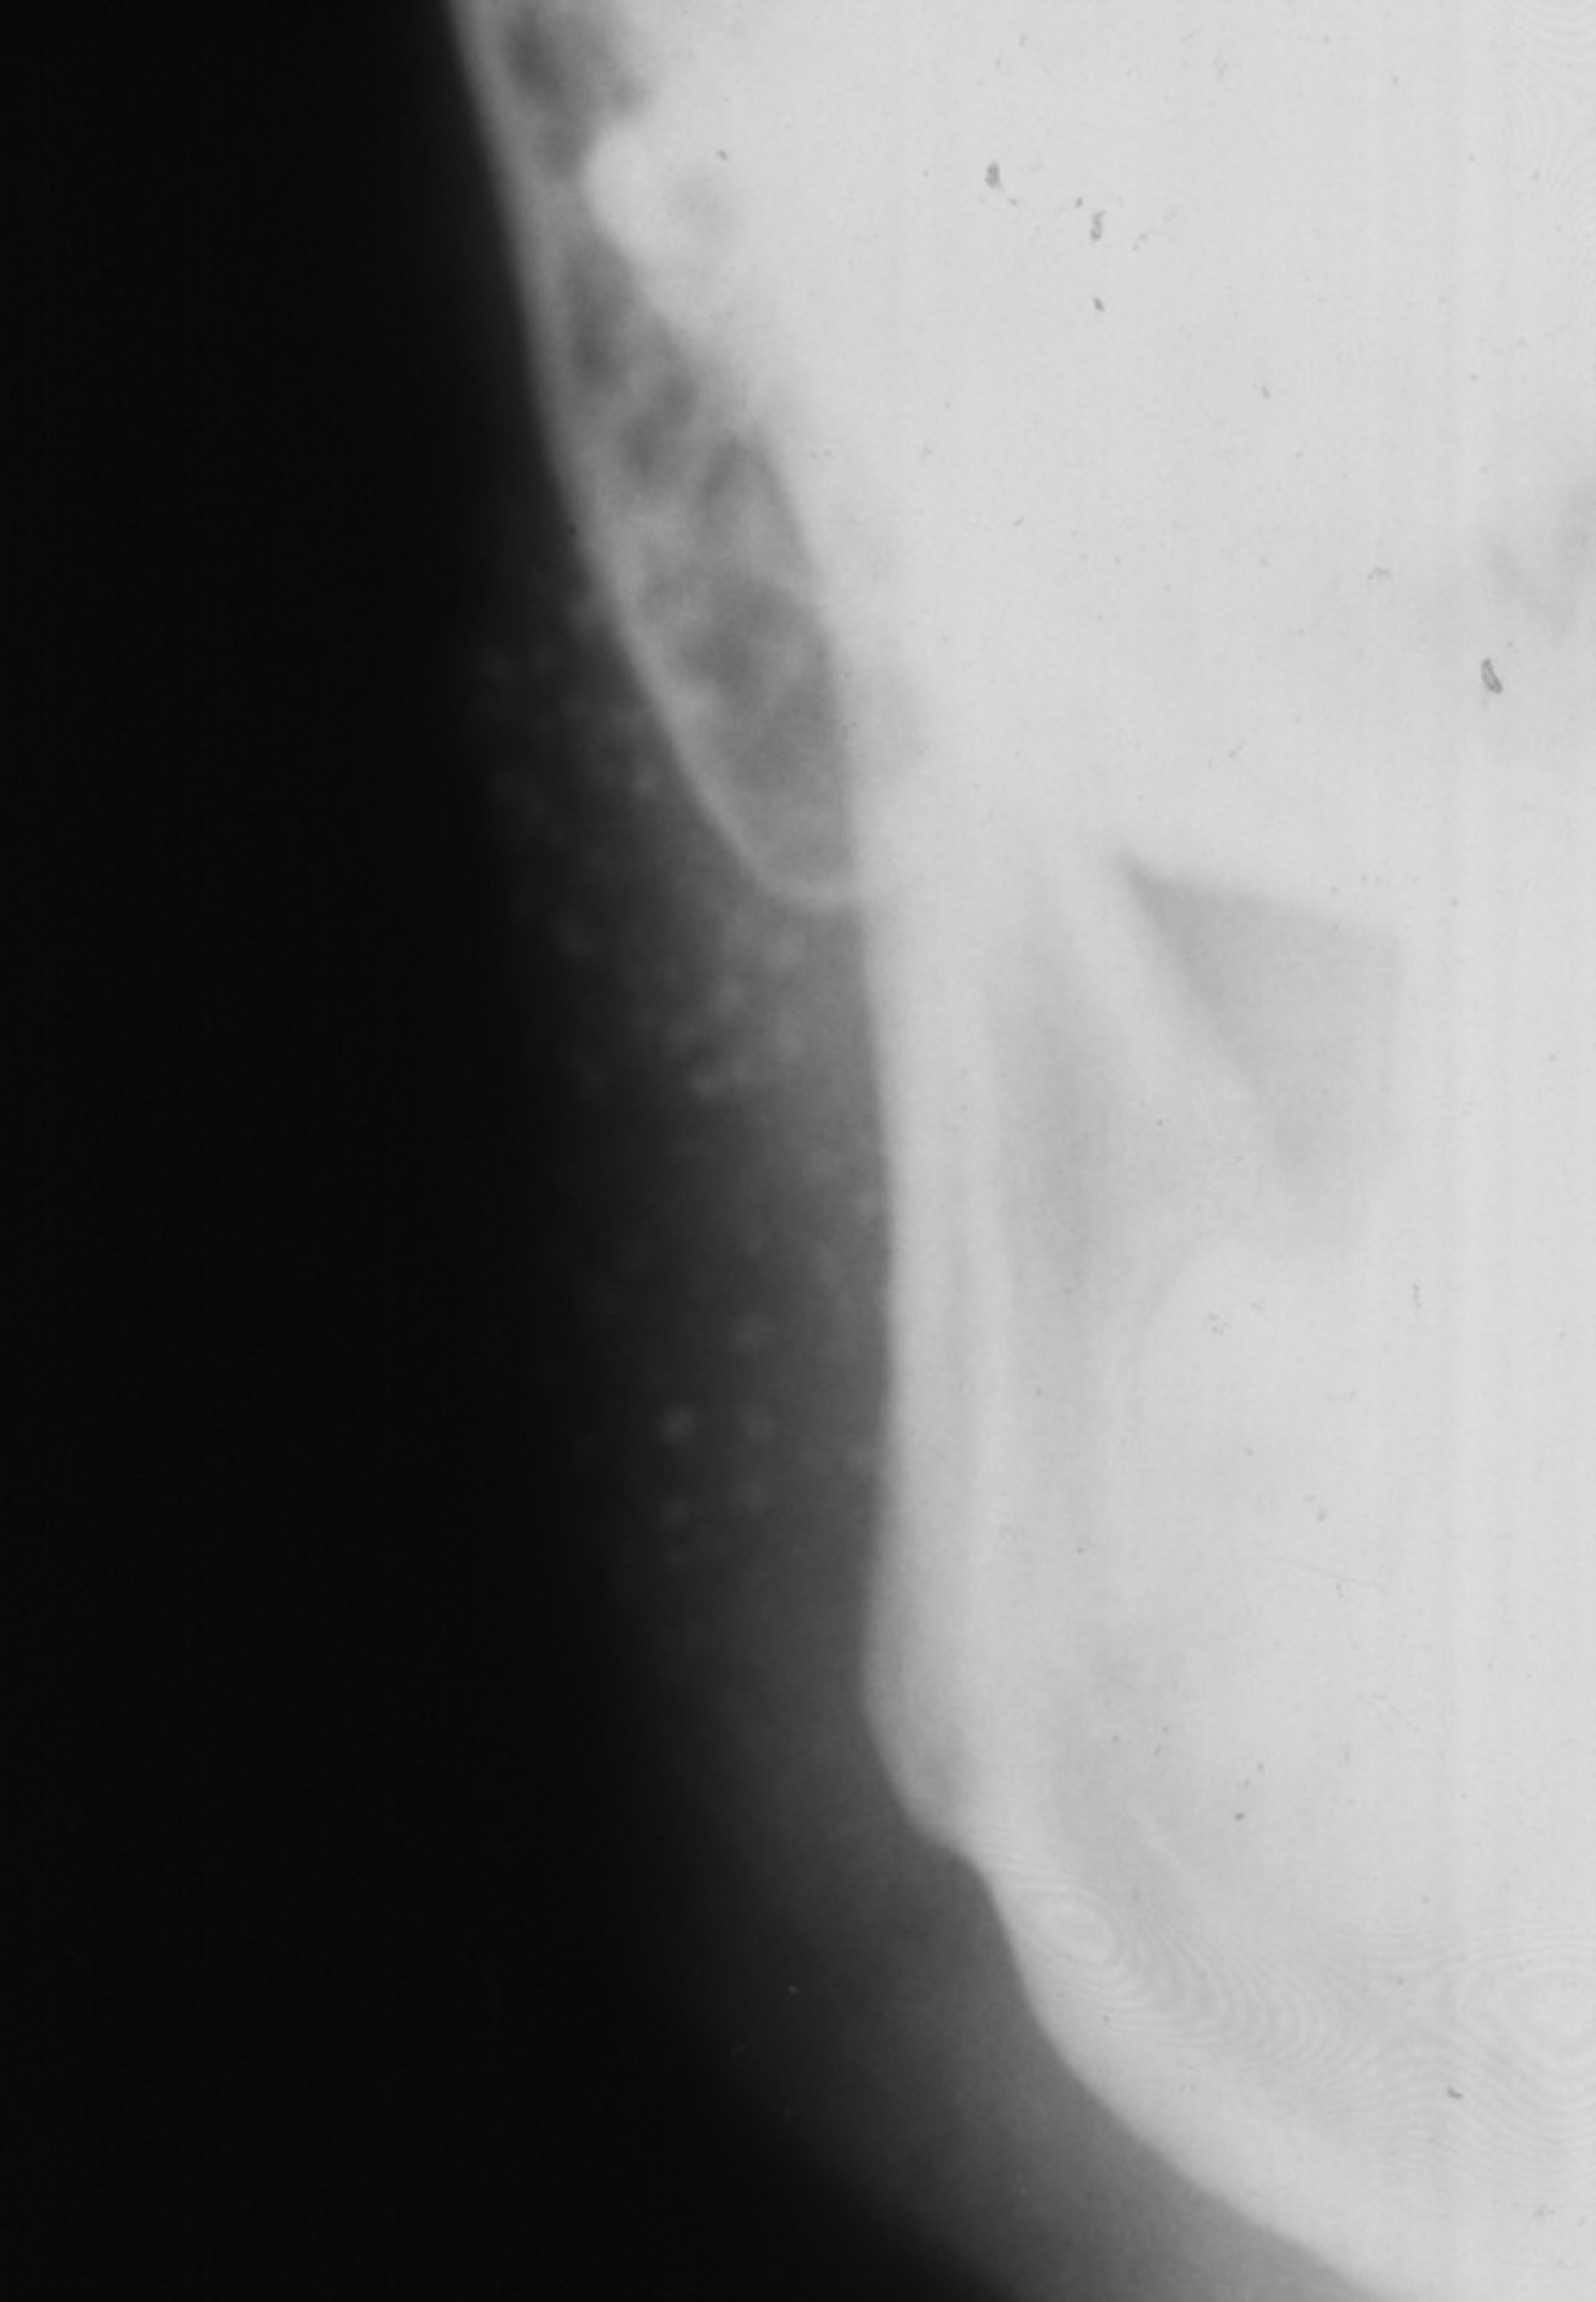

Fig 6. Sialogram showing a Christmas-tree pattern and uniform shape of the right parotid gland.

Table 6

Imaging analyses, including ultrasonography and sialography, of the parotid glands were performed. Ultrasonographic features of the cervical region did not show any alterations of the submandibular and left parotid glands (Figure 2 through Figure 5). However, the right parotid gland demonstrated an inhomogeneous structure of the gland with scattered, multiple, small, oval, hypoechoic, or anechoic areas, usually well defined, and increased parenchymal blood flow. Sialographic examination of the right parotid gland showed a snowflake-like form and Christmas-tree pattern and evidence of sialoangiectasia without any changes of duct anatomy (Figure 6). Even after the salivary stimulation, the duct system was kept filled by the contrast fluid that again highlighted the sialectatic changes (Figure 7).